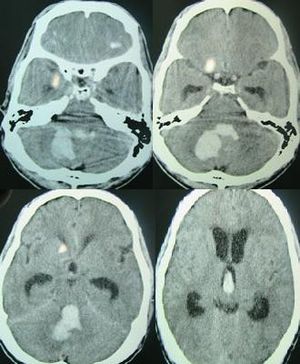

뇌출혈 진단은 일반적으로 CT 스캔을 통해 이루어진다.[60] CT 스캔에서 뇌출혈은 혈액이 다른 조직보다 밝게 나타나기 때문에 식별할 수 있다. 출혈 주변 조직은 부종으로 인해 뇌의 나머지 부분보다 밀도가 낮아 CT 스캔에서 더 어둡게 나타난다.[28] 출혈 주변의 부종은 처음 48시간 동안 빠르게 증가하고 14일째에 최대 크기에 도달하며, 혈종의 크기가 클수록 주변 부종도 커진다.[29]

혈액이 혈관 밖으로 유출되면 응고되어 혈장 성분이 흡수되므로 헤모글로빈 농도가 상승한다. 따라서 CT에서는 고흡수역을 나타내 진단이 비교적 용이하다. 혈종량(ml)은 최대 장경(cm) × 최대 단경(cm) × 슬라이스 두께(cm) × 슬라이스 수 / 2 로 추정한다.

고혈압성 출혈은 피각, 시상, 교, 소뇌나 대뇌 피질하에 호발한다. 이러한 부위 이외에 혈종이 존재하는 경우에는 뇌 동정맥 기형, 해면상 혈관종 등의 뇌혈관 기형, 아밀로이드 혈관병증, 뇌종양, 출혈성 경색, 혈액 응고 이상을 동반한 출혈 등 다른 원인도 고려한다.